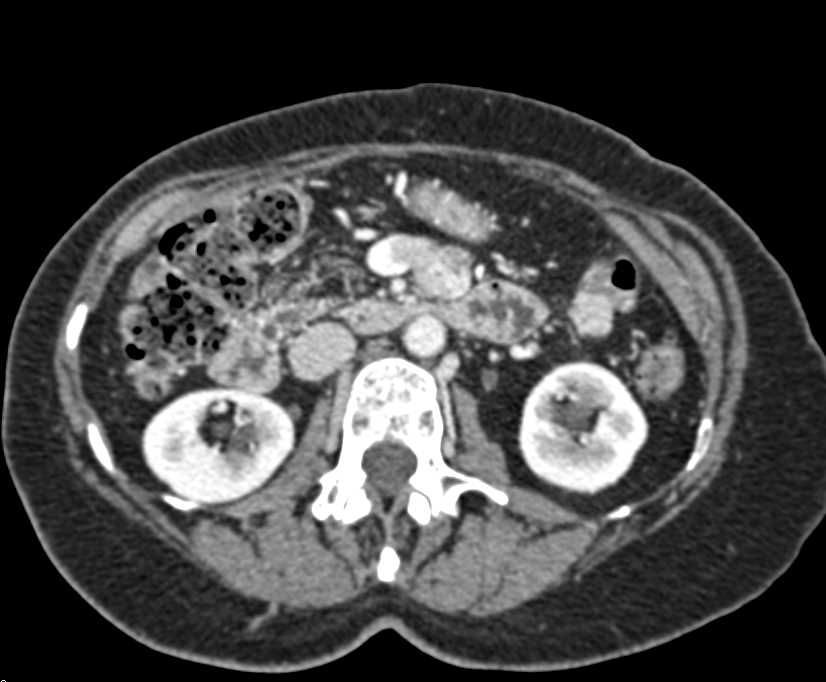

Intraductal Papillary Mucinous Neoplasm (IPMN) in Head of Pancreas with Small Arteriovenous (AV) Shunts Liver